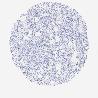

SKIN CANCER - Protein expressioni

A mouse-over function shows sample information and annotation data. Click on an image to view it in a full screen mode. Samples can be filtered based on level of antibody staining by selecting one or several of the following categories: high, medium, low and not detected. The assay and annotation is described here.

Each image is clickable and will lead to virtual microscopy that enables deeper exploration of all samples and also displays staining intensity scores, fraction scores and subcellular localization as well as patient and tissue information for each sample.

Antibody HPA038925

Basal cell carcinoma